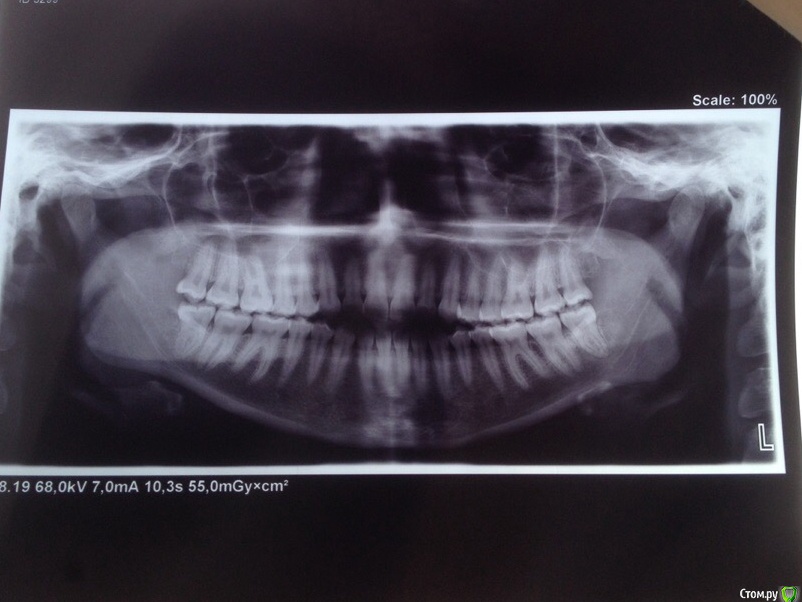

КошкинДом Опубликовано 3 сентября, 2019 Поделиться Опубликовано 3 сентября, 2019 Приветствую всех!Меня зовут Александра, мне 25 лет и я ипохондрик, переживаю в данный момент из-за своих зубов. Возможно кто-то из вас сможет дать мне совет Пол года назад у меня немного заболел левый ВНЧС, было неудобно спасть, затем все прошло и больше ничего не беспокоит до сих пор, только иногда хрустит в левом суставе и легкий дискомфорт в ухе после еды. Я заметила что в течении этих 6 месяцев мой прикус открылся ~2мм Вот мое фото 2017:А вот сейчас: Также прикрепляю два фото, ТРГ и ОПТГ: Мой вопрос: Меня сейчас ничего не беспокоит в моих зубах, можно ли и дальше спокойно жить? Если кто-то сталкивался с подобным дайте совет Всем хорошего дня 1 Ссылка на комментарий

КошкинДом Опубликовано 4 сентября, 2019 Автор Поделиться Опубликовано 4 сентября, 2019 Заключение ТРГ: скелетный 1 класс с выраженной тенденцией к 3 классу. Вертикальная резцовая дизокклюзия зубоальвеолярная форма. Протрузия резцов верхней челюсти. Нейтральный тип роста челюстей с тенденцией к вертикальному.Сужение нижних воздухоносных путей не выявлено. Ссылка на комментарий